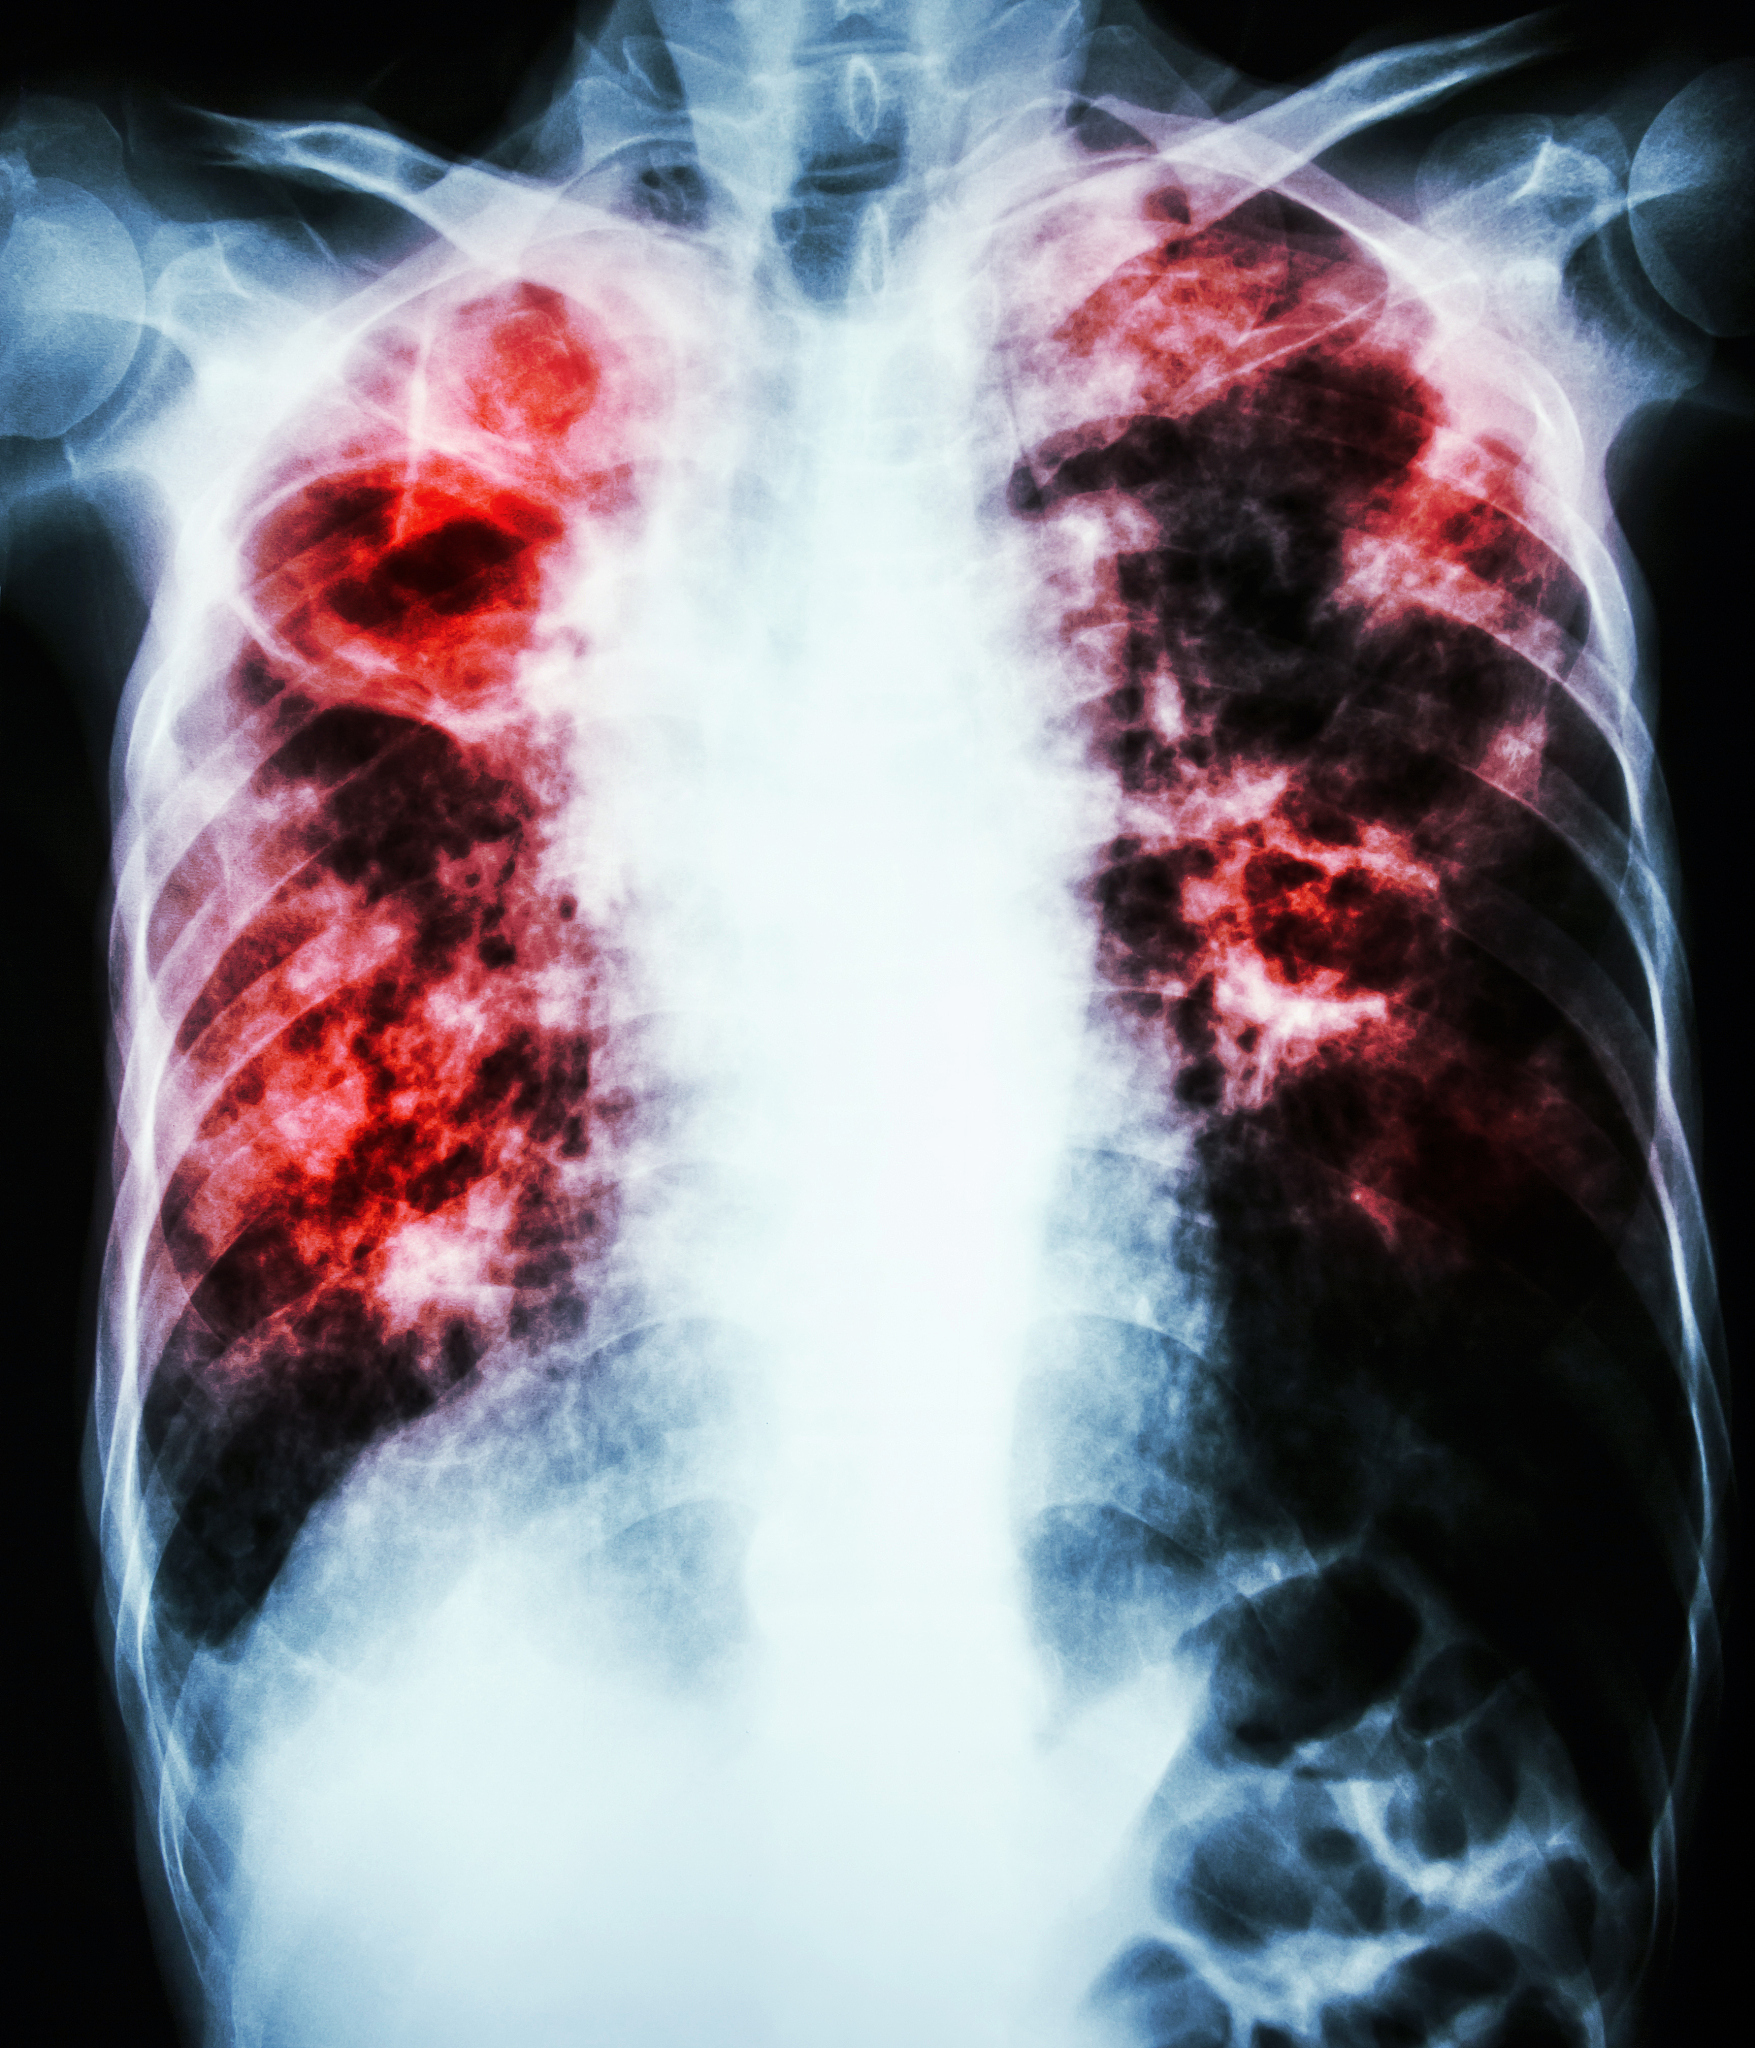

The 2019 coronavirus disease (COVID-19), caused by severe acute respiratory syndrome coronavirus 2 (SARS-CoV-2), has resulted in significant global morbidity and mortality. The World Health Organization declared it a pandemic in March 2020 due to its rapid spread and impact [1]. COVID-19 presents with a diverse spectrum of clinical manifestations, ranging from asymptomatic or pre-symptomatic stages to mild respiratory symptoms, severe pneumonia, acute respiratory distress syndrome, multi-organ dysfunction, and even death.

In addition to these factors, the incidence and characteristics of bacterial, fungal, and viral co-infections in COVID-19 patients have emerged as a significant area of research interest [4]. These co-infections can complicate the clinical course of COVID-19 and pose unique challenges in diagnosis and treatment.

However, there remains a paucity of research investigating the clinical characteristics and co-infection profiles of hospitalized COVID-19 patients across different severity levels. This knowledge gap is partly attributable to the limitations of traditional microbial detection methods, such as prolonged turnaround times for results and suboptimal sensitivity, which hinder comprehensive understanding of co-infection patterns in this patient population.

This study aims to address this critical gap in knowledge by investigating the demographic characteristics, laboratory indicator differences, and co-infection profiles of COVID-19 patients with varying severity levels in the post-outbreak period in China. To overcome the limitations of conventional diagnostic approaches, this study will employ targeted next-generation sequencing (tNGS), a cutting-edge technology known for its high sensitivity and broad pathogen detection capabilities. This comprehensive approach will provide valuable insights into the clinical heterogeneity of COVID-19 and contribute to the development of more effective, personalized management strategies for this complex and evolving disease.